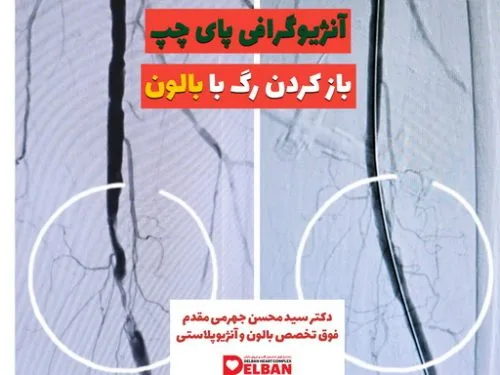

- دکتر سید محسن جهرمی مقدم

- آنژیوگرافی کرونری

- آنژیوپلاستی کرونری

- انسداد شریانهای اندام تحتانی(PAD)

- بیماری عروق محیطی